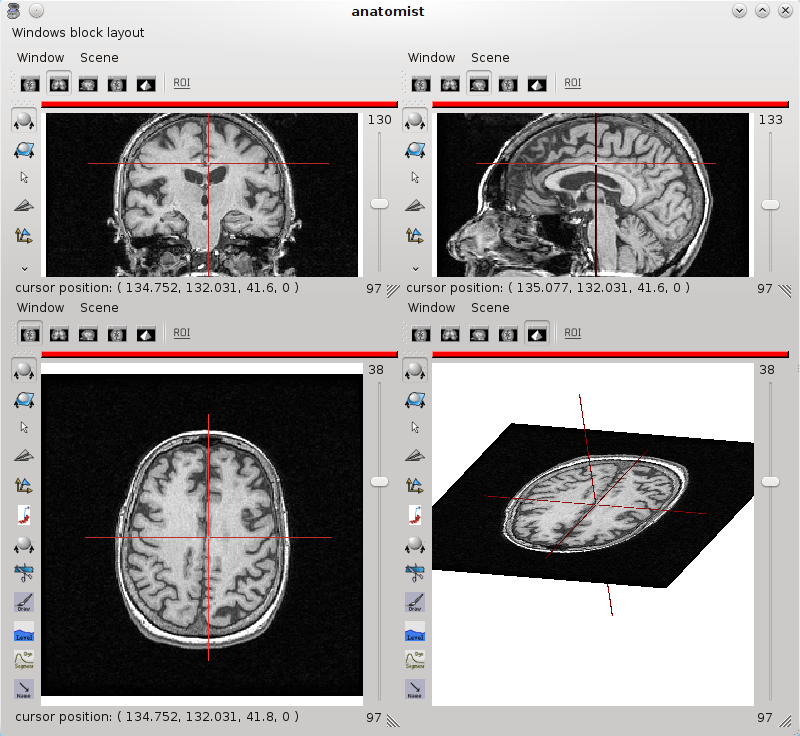

It is possible to open several views using the menu Windows -> Open 3D standard views or Open a 4 views block. A block is a window that can contain several views. To add a window in a block, drag and drop the window item from Anatomist’s list of windows to the block. To remove it, use the window menu Window => Detach window

4 views block¶